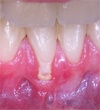

Photos extraites du diaporama :